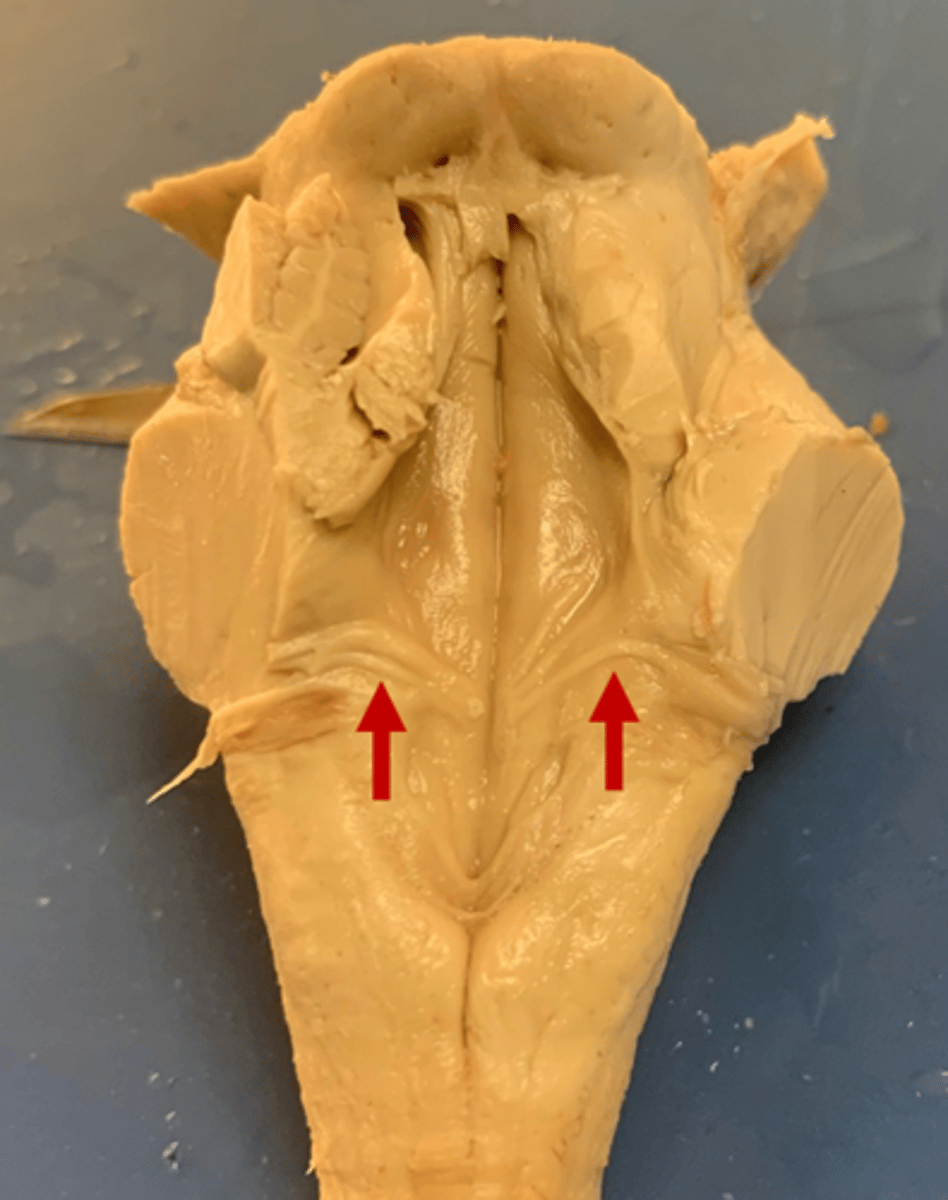

two ridges of tissue on the ventral aspect of the medulla, separated from each other by the ventral median fissure

pyramids

area where most corticospinal fibers decussate over the lower medulla, therefore obscuring the ventral median fissure

pyramidal decussation

elongated mounds of tissue lateral to the medullary pyramids

olives

vertical groove dorsolateral to the inferior olive on each side that gives rise to CN IX and X

postolivary sulcus

white matter stalks that connect the medulla to the cerebellum

**these help to form the lateral walls of the caudal portion of the 4th ventricle

inferior cerebellar peduncles

medial paired ridges of tissue on the dorsal aspect of the closed portion of the medulla

tractus gracilis

lateral paired ridges of tissue on the dorsal aspect of the closed portion of the medulla

tractus cuneatus

superior ends of the medial paired ridges of tissue on the dorsal aspect of the closed portion of the medulla, formed by namesake nuclei

gracilis tubercles

superior ends of the lateral paired ridges of tissue on the dorsal aspect of the closed portion of the medulla, formed by namesake nuclei

cuneatus tubercles

V-shaped boundary of the caudal aspect of the 4th ventricle that marks the boundary between the open and closed portions of the medulla

obex

pyramids

ventral median fissure

pyramidal decussation

C

inferior cerebellar peduncles

cuneate tubercle

gracilis tubercle

cuneatus tract

gracilis tract

obex